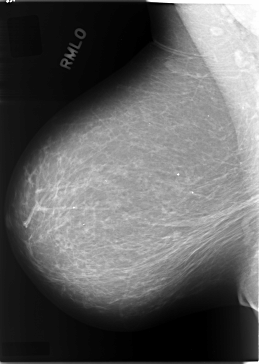

C_0084_1.RIGHT_MLO

RIGHT_CC LINES 5960 PIXELS_PER_LINE 3688 BITS_PER_PIXEL 12 RESOLUTION 50 NON_OVERLAY

RIGHT_MLO LINES 5824 PIXELS_PER_LINE 4136 BITS_PER_PIXEL 12 RESOLUTION 50 NON_OVERLAY